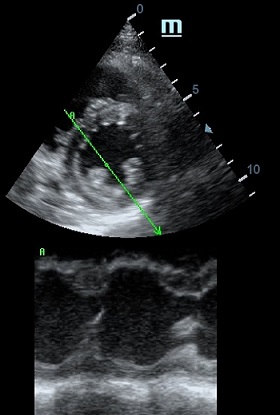

TAPSE - показатель амплитуды движения латеральной части кольца трикуспидального клапана, позволяет количественно и быстро оценить систолическую функцию правого желудочка, норма которого составляет более 17 мм. Главным условием является проведение линии М-режима параллельно стенке правого желудочка в апикальном четырех камерном сечении, что легко достигается при Free Xros.